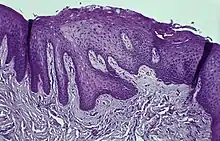

Fig.3. Hematoxylin Eosin staining of the attached gingiva with a Retrocuspid papilla.

Immunohistochemical staining with FXIIIa [9] antibody disclosed a population of reactive spindle- or stellate-shaped cells[10] in 11 of 15 cases, located in connective tissue papillae and in a few cases also distributed throughout the lesion. The FXIIIa-stained cells appeared together with the frequently observed stellate, "young" occasionally multinucleated fibroblastic cells observed in more than 50% of patients aged 10–69 years. It is likely that FXIIIA-expressing "mucosal dendrocytes" are pathologically involved in some way.[11][12][13]